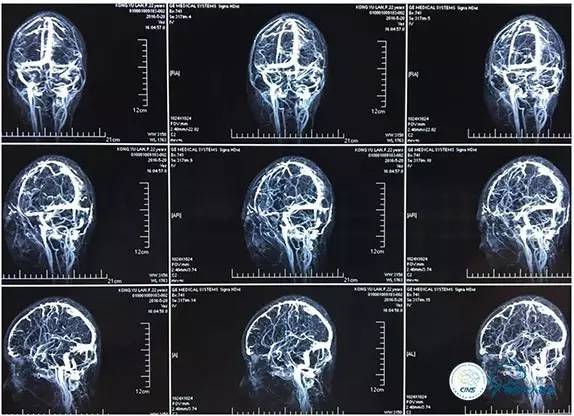

MRV

2016-05-20 MRV

磁共振黑血系列